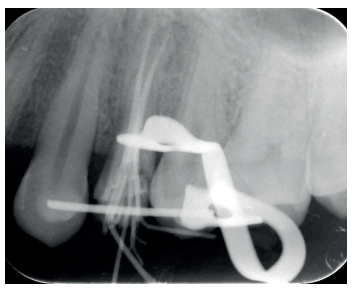

Una vez se hubo posicionado el diente 2 mm supragingival, se procedió a la ferulización con alambre de acero a los dientes adyacentes (Figuras 3 y 4) y la eliminación de cualquier tipo de oclusión, utilizando topes oclusales en los segundos molares inferiores. La ferulización se mantuvo durante dos semanas, coincidiendo con el momento de la endodoncia (Figura 5). El paciente fue citado para las revisiones periódicas y posteriormente para la rehabilitación del diente, una vez hubieron concurrido 6 semanas desde la extrusión, en las que se haya obtenido una cicatrización de los tejidos de soporte supracrestales10. En este momento, tras comprobar signos clínicos, periodontales y radiográficos saludables, se citó al paciente para el tallado y la confección mediante flujo digital (Cerec® System) de una endocorona de disilicato de litio (e.max®, Ivoclar Vivadent). El acondicionamiento de la corona se realizó con ácido fluorhídrico y silano, y para la cementación se utilizó cemento de resina (Calibra®, Dentsply Sirona).

adyacentes, tras la extrusión quirúrgica.